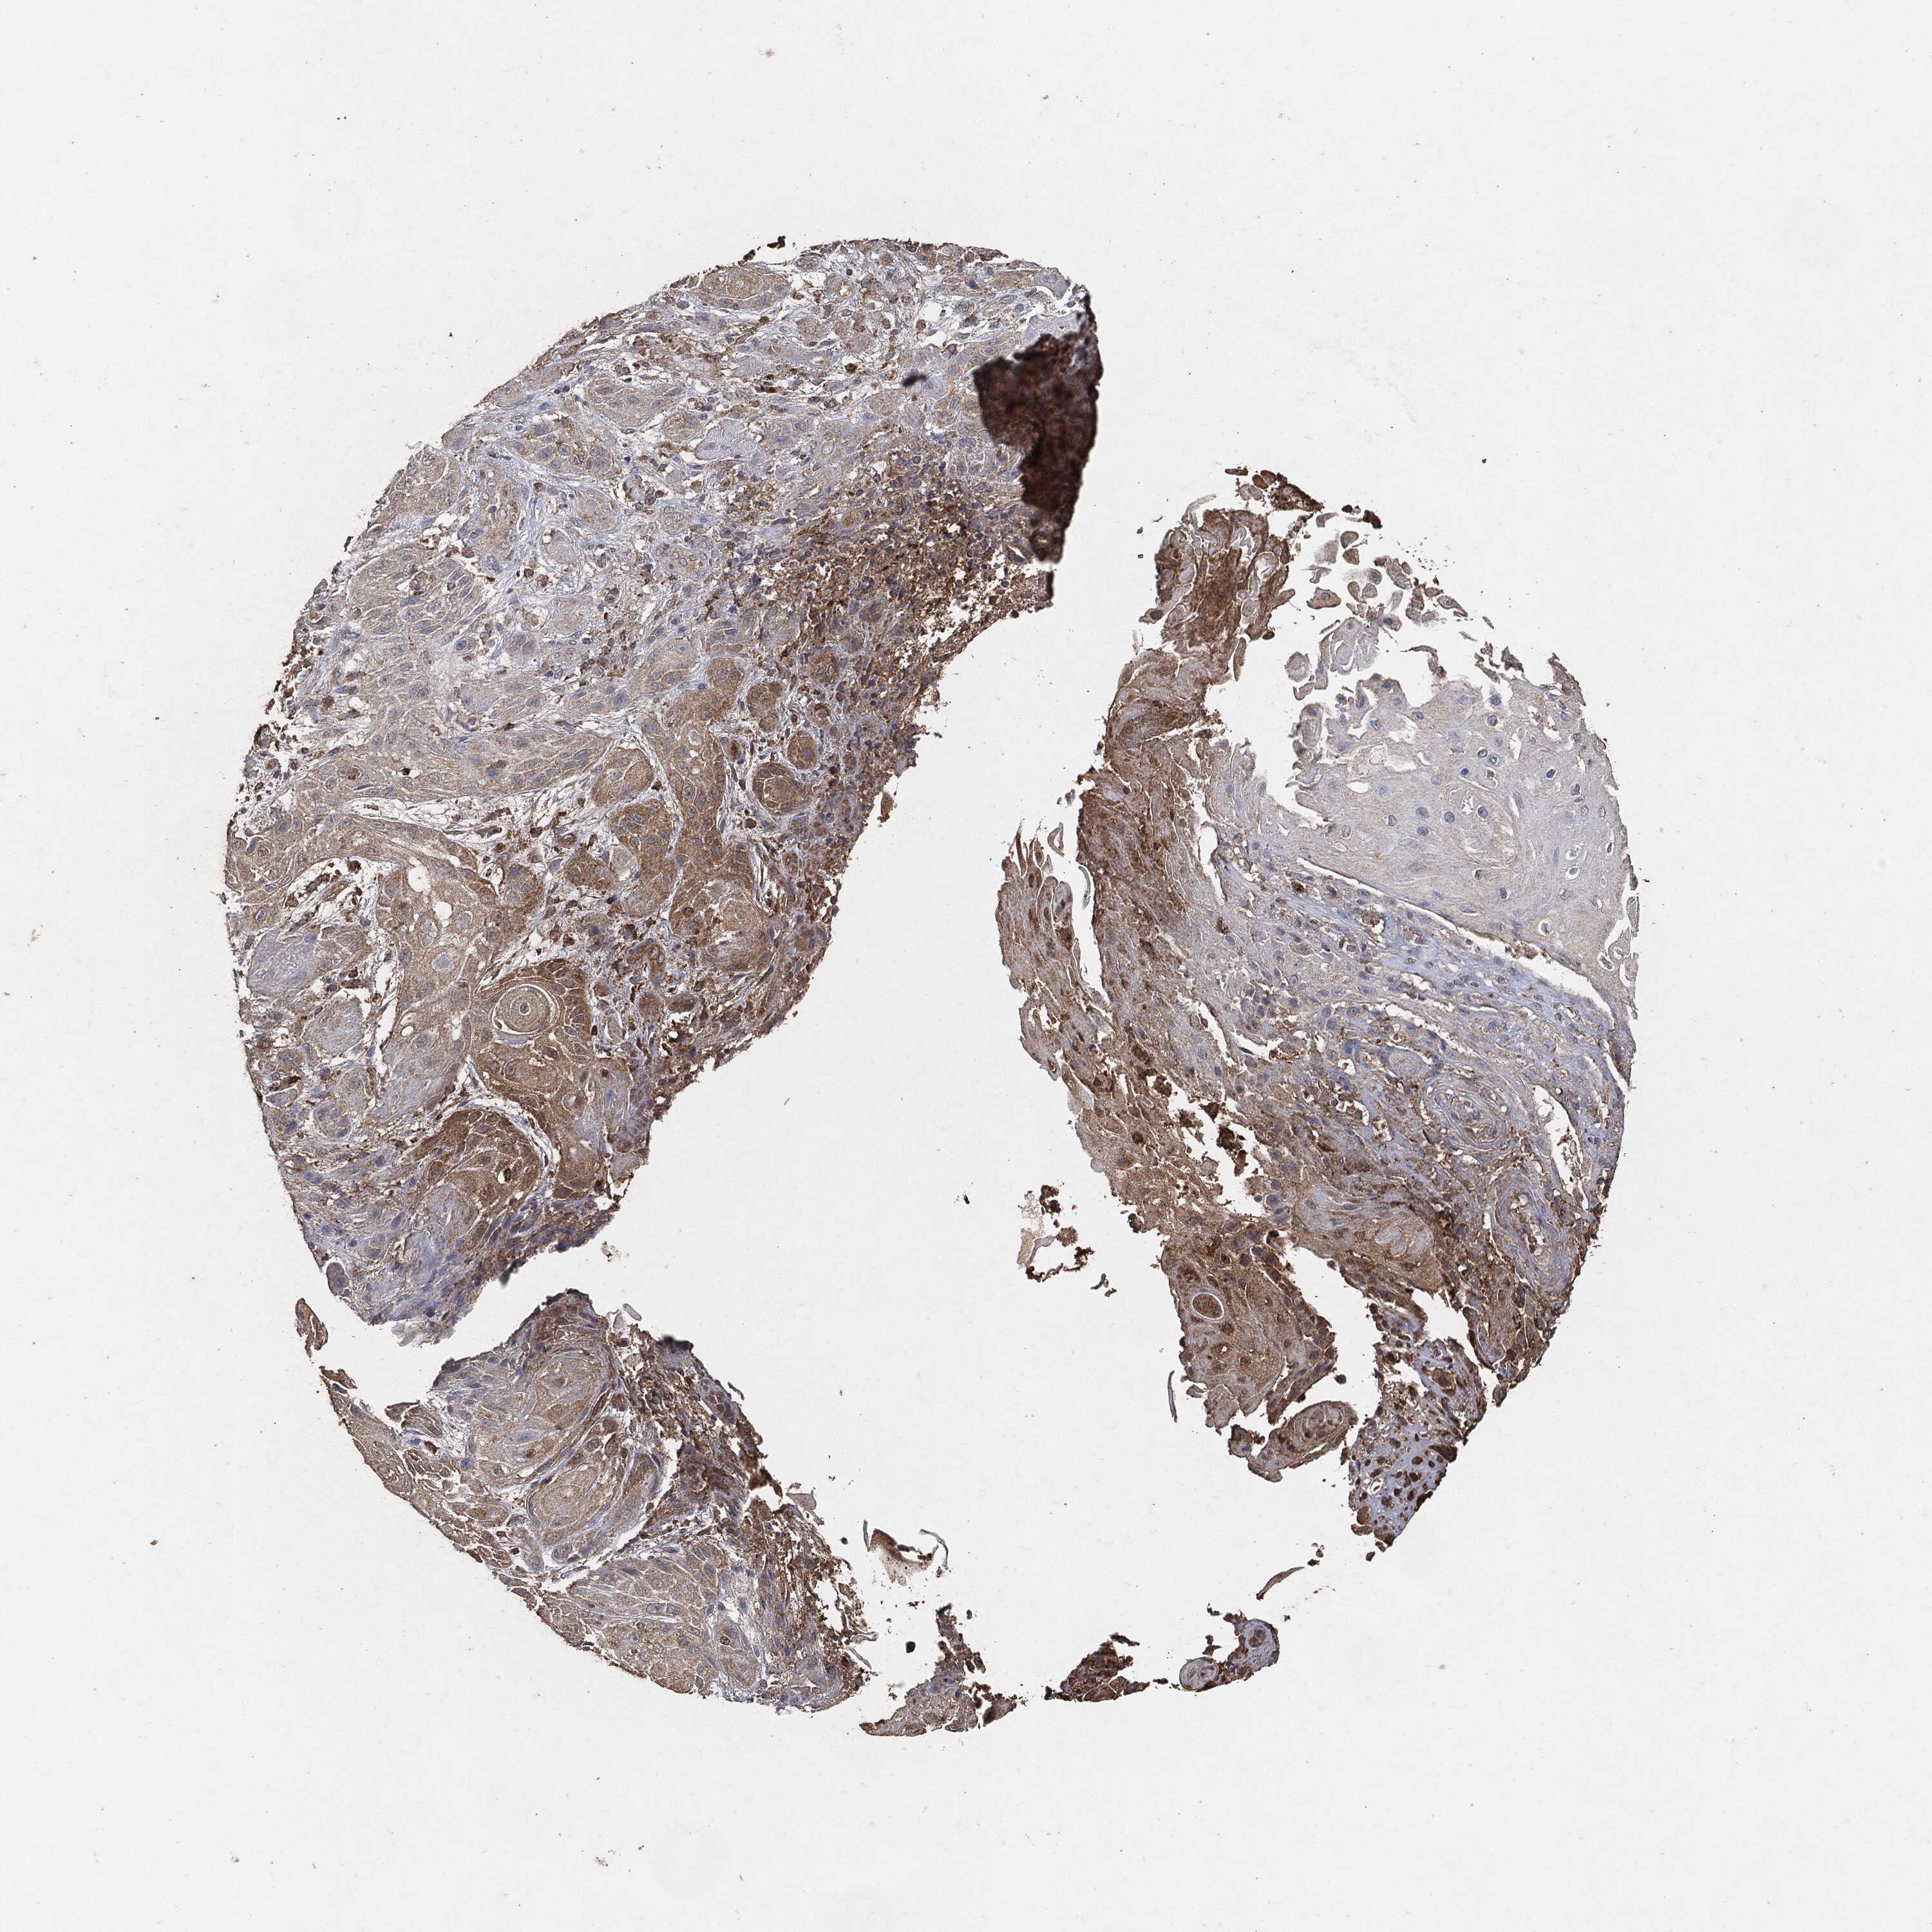

SKIN CANCER - Protein expressioni

A mouse-over function shows sample information and annotation data. Click on an image to view it in a full screen mode. Samples can be filtered based on level of antibody staining by selecting one or several of the following categories: high, medium, low and not detected. The assay and annotation is described here.

Antibody stainingi

Antibody staining in the annotated cell types in the current human tissue is reported as not detected, low, medium, or high, based on conventional immunohistochemistry profiling in selected tissues. This score is based on the combination of the staining intensity and fraction of stained cells.

Each image is clickable and will lead to virtual microscopy that enables deeper exploration of all samples and also displays staining intensity scores, fraction scores and subcellular localization as well as patient and tissue information for each sample.

Squamous cell carcinoma, NOS